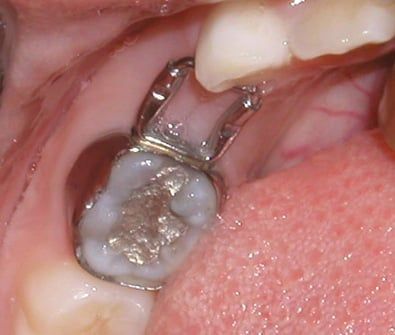

Spring Digitalizer

This appliance is indicated when one molar (an erupting six-year molar) is caught under the edge of a primary second molar. The appliance features a wire spring which is attached to the erupting molar and to the second molar. The spring provides the force to move the erupting molar into proper position.